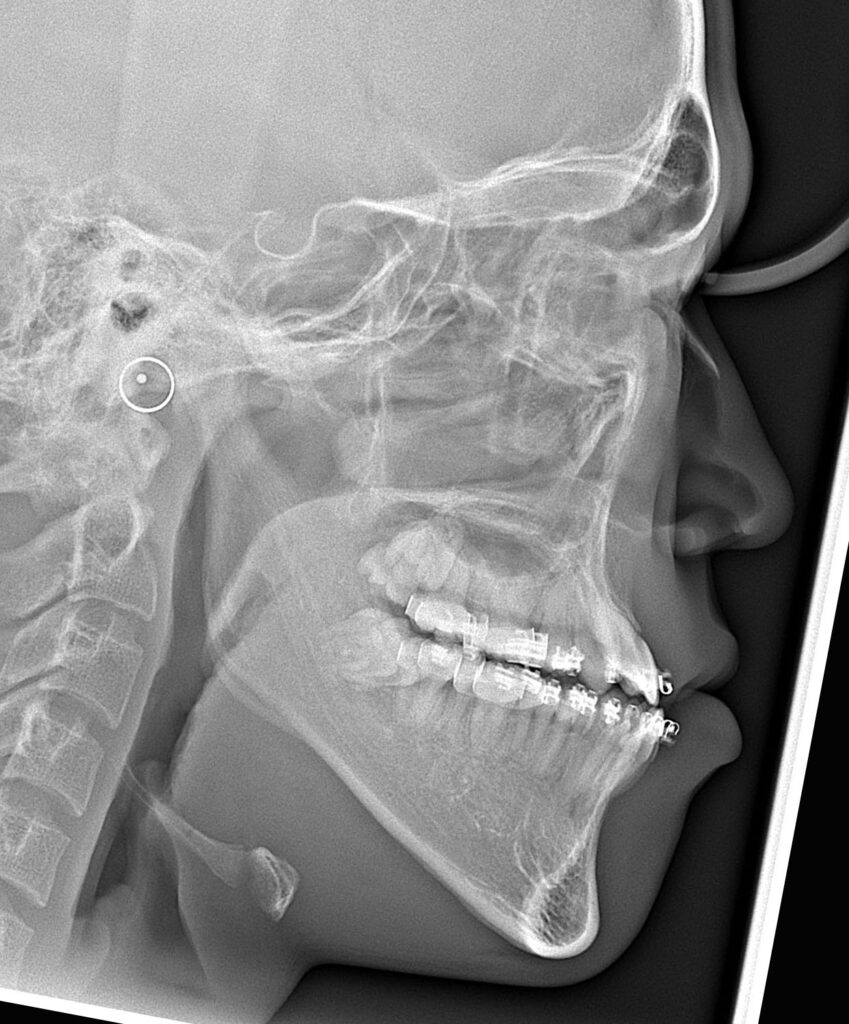

術前後のセファログラムを以下に示します。

手術は、上顎に対してLe Fort I型骨切り術、下顎に対して下顎枝矢状分割骨切り術(SSRO)を施行しました。

顔面高を減じる目的で上顎を上方移動させ、さらに開咬を確実に閉鎖するため、上顎骨・下顎骨複合体を時計回転させる術式を選択しました。